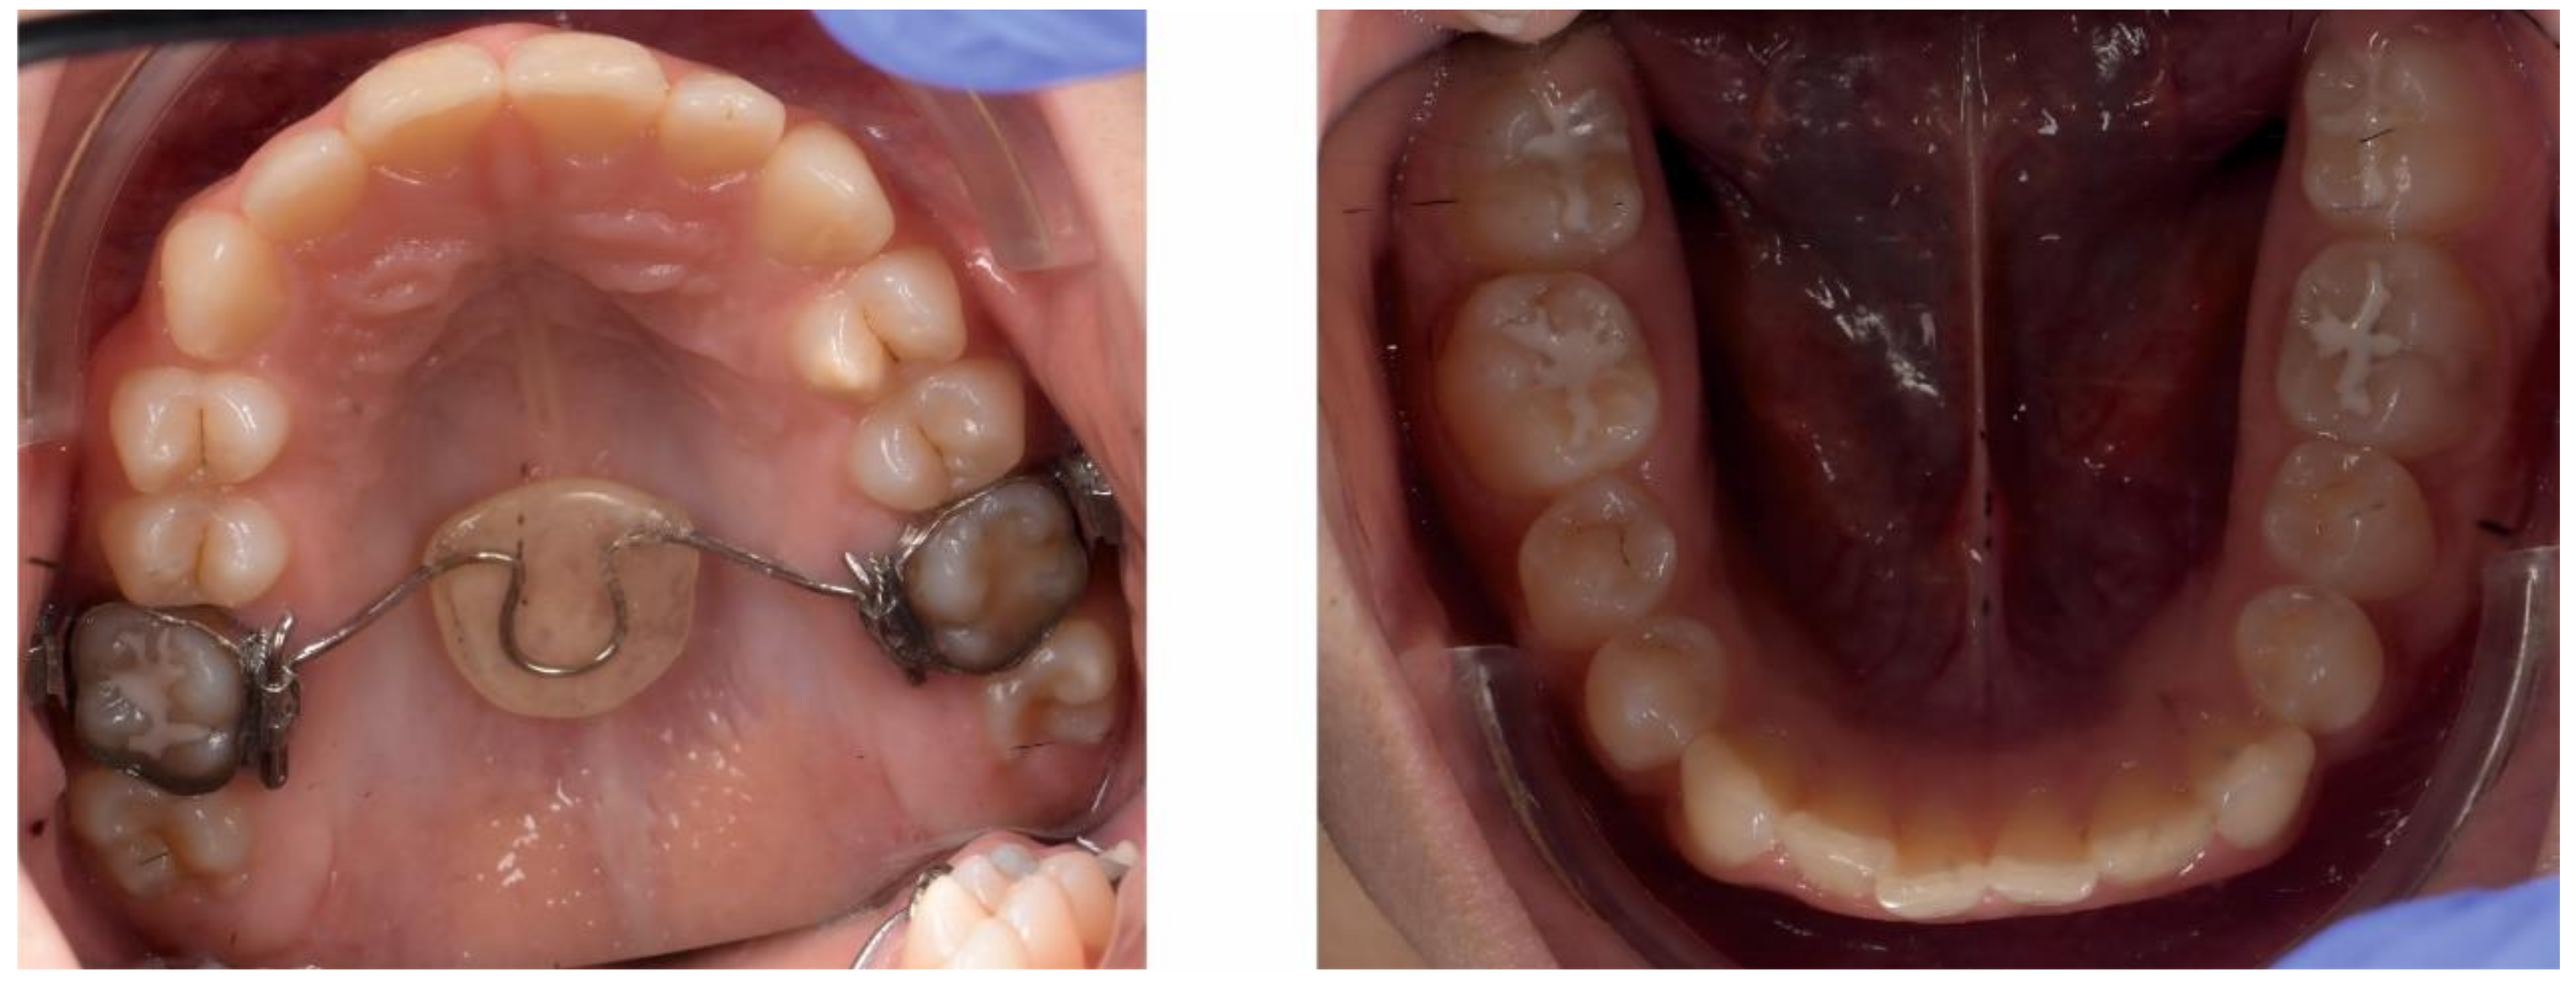

2.3.2. Second Phase of Treatment—2017—Bite-Blocks and Transpalatal Arch